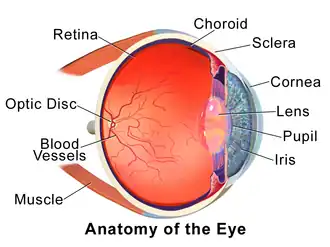

The eye can be considered as a living optical device. It is approximately spherical in shape, with its outer layers, such as the outermost, white part of the eye (the sclera) and one of its inner layers (the pigmented choroid) keeping the eye essentially light tight except on the eye's optic axis. In order, along the optic axis, the optical components consist of a first lens (the cornea—the clear part of the eye) that accounts for most of the optical power of the eye and accomplishes most of the focusing of light from the outside world; then an aperture (the pupil) in a diaphragm (the iris—the coloured part of the eye) that controls the amount of light entering the interior of the eye; then another lens (the crystalline lens) that accomplishes the remaining focusing of light into images; and finally a light-sensitive part of the eye (the retina), where the images fall and are processed. The retina makes a connection to the brain via the optic nerve. The remaining components of the eye keep it in its required shape, nourish and maintain it, and protect it.

The eye is not shaped like a perfect sphere; rather it is a fused two-piece unit, composed of an anterior (front) segment and the posterior (back) segment. The anterior segment is made up of the cornea, iris and lens. The cornea is transparent and more curved and is linked to the larger posterior segment, composed of the vitreous, retina, choroid and the outer white shell called the sclera. The cornea is typically about 11.5 mm (0.45 in) in diameter, and 0.5 mm (500 μm) in thickness near its centre. The posterior chamber constitutes the remaining five-sixths; its diameter is typically about 24 mm (0.94 in). An area termed the limbus connects the cornea and sclera. The iris is the pigmented circular structure concentrically surrounding the centre of the eye, the pupil, which appears to be black. The size of the pupil, which controls the amount of light entering the eye, is adjusted by the iris' dilator and sphincter muscles.

Light energy enters the eye through the cornea, through the pupil and then through the lens. The lens shape is changed for near focus (accommodation) and is controlled by the ciliary muscle. Between the two lenses (the cornea and the crystalline lens), there are four optical surfaces which each refract light as it travels along the optical path. One basic model describing the geometry of the optical system is the Arizona Eye Model.[2] This model describes the accommodation of the eye geometrically. Photons of light falling on the light-sensitive cells of the retina (photoreceptor cones and rods) are converted into electrical signals that are transmitted to the brain by the optic nerve and interpreted as sight and vision.

The eye is made up of three coats, or layers, enclosing various anatomical structures. The outermost layer, known as the fibrous tunic, is composed of the cornea and sclera, which provide shape to the eye and support the deeper structures. The middle layer, known as the vascular tunic or uvea, consists of the choroid, ciliary body, pigmented epithelium and iris. The innermost is the retina, which gets its oxygenation from the blood vessels of the choroid (posteriorly) as well as the retinal vessels (anteriorly).

The spaces of the eye are filled with the aqueous humour anteriorly, between the cornea and lens, and the vitreous body, a jelly-like substance, behind the lens, filling the entire posterior cavity. The aqueous humour is a clear watery fluid that is contained in two areas: the anterior chamber between the cornea and the iris, and the posterior chamber between the iris and the lens. The lens is suspended to the ciliary body by the suspensory ligament (zonule of Zinn), made up of hundreds of fine transparent fibers which transmit muscular forces to change the shape of the lens for accommodation (focusing). The vitreous body is a clear substance composed of water and proteins, which give it a jelly-like and sticky composition.[6]